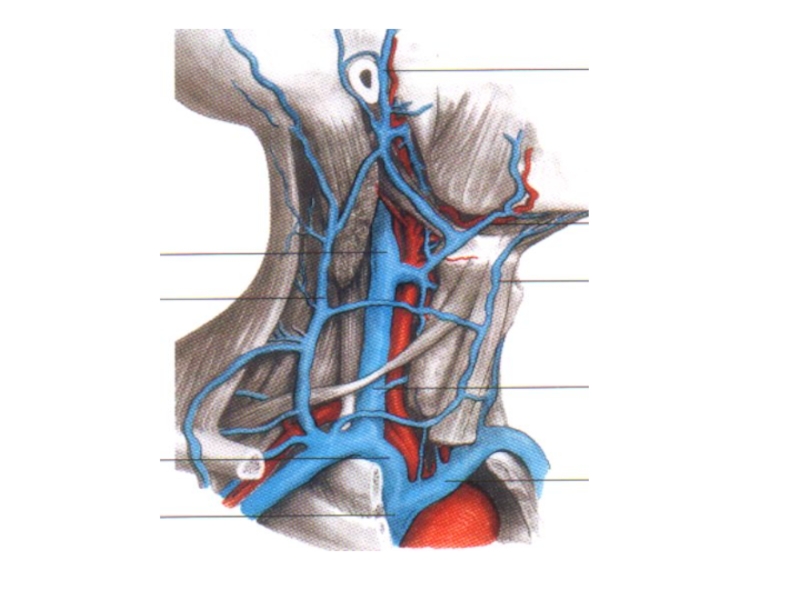

Анатомия внутренней яремной вены: КТ изображения